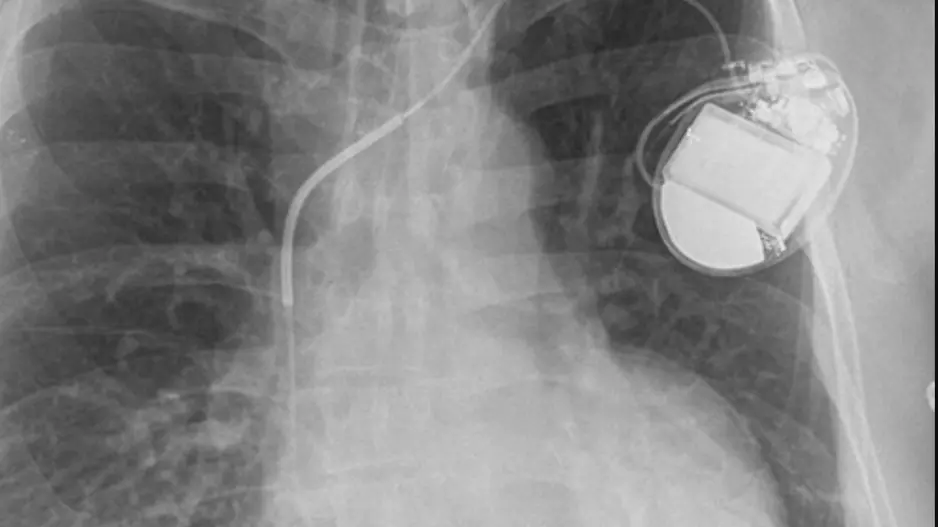

Medtronic has gained European CE mark approval for its Aurora EV-ICD MRI SureScan and Epsila EV MRI SureScan defibrillation lead, which are designed to help treat severe heart rhythm issues.

The most common causes of mortality during transvenous lead removal (TLR) in patients with cardiac implantable electronic devices (CIEDs) are infection and decompensated heart failure, according to new research published in JACC:…